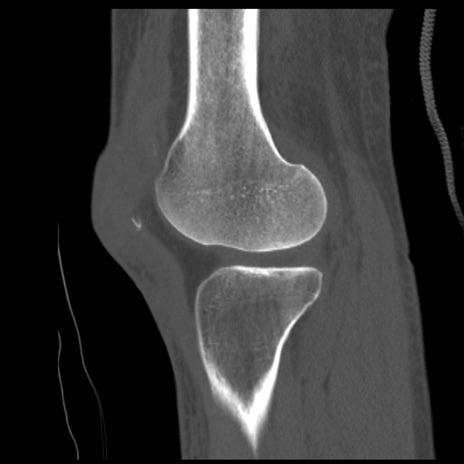

症例28 右膝関節CT(矢状断像)

右膝関節CT

冠状断像